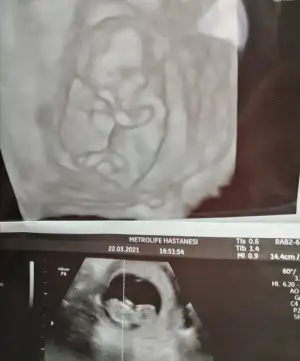

Ay masallah ne minikler yaaKızlar doktordan geldim cinsiyet için erkek olabilir dedi ama henüz çok erken 2 haftaya net belli olur dedi bugün 12 haftalığım![]()

Süperrrrr yaaa ne güzel beybiyi gördün geldinKızlar doktordan geldim cinsiyet için erkek olabilir dedi ama henüz çok erken 2 haftaya net belli olur dedi bugün 12 haftalığım![]()

Maşallah canımKızlar doktordan geldim cinsiyet için erkek olabilir dedi ama henüz çok erken 2 haftaya net belli olur dedi bugün 12 haftalığım![]()

Metrolifeda hangi doktora gittin canım? Annem geçen orda Tuna hanıma gitmiş çok beğendi. Bu sefer geldiğinde bi tanışmak amaçlı görün dediAyy iple çekersin şimdi perşembe ben çarşamba tekrar gideceğim çok sık usg oldu bana ama napim :)

Bu arada usg fotodan gördüm metrolife gittiğiniAyy iple çekersin şimdi perşembe ben çarşamba tekrar gideceğim çok sık usg oldu bana ama napim :)

Ay tunayı bende duydum iyimiş ama ben oksapar iğne yazdırma amaçlı sırası en boş doktora gittim Kenan gengeç hoca. Biz biraz ısrar ettik cinsiyet için o da bişeyler çıkarımda bulundu 2 hafta sonra tekrar bakılsın o zaman belli olur dedi. Ben normalde Bülent sezgine gidiyorum kendi kliniğineMetrolifeda hangi doktora gittin canım? Annem geçen orda Tuna hanıma gitmiş çok beğendi. Bu sefer geldiğinde bi tanışmak amaçlı görün dedi![]()

Aynen canımBu arada usg fotodan gördüm metrolife gittiğini![]()